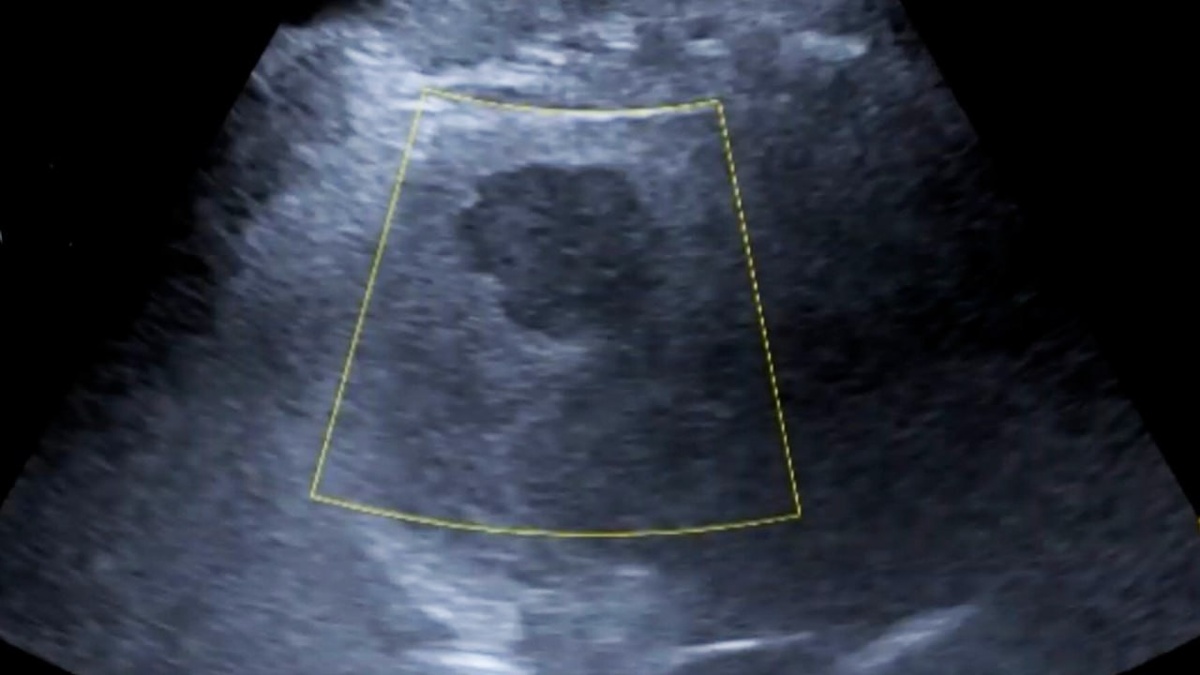

Врачи из Охи и Москвы вместе выявили образования в печени у пациентки В Охе врачи при помощи телеконсультации с московскими коллегами обследовали 32-летнюю пациентку, у которой впервые выявили объёмные образования в печени. Совместная работа специалистов, разделённых расстоянием более семи тысяч километров, позволила спланировать дальнейшую диагностику и лечение. 🔵 Подпишись на ТВ «ОХА» | Прислать новость ✉️ Получи денежное вознаграждение 🪙

В Охе врачи при помощи телеконсультации с московскими коллегами обследовали 32-летнюю пациентку, у которой впервые выявили объёмные образования в печени. Совместная работа специалистов, разделённых расстоянием более семи тысяч километров, позволила спланировать дальнейшую диагностику и лечение.